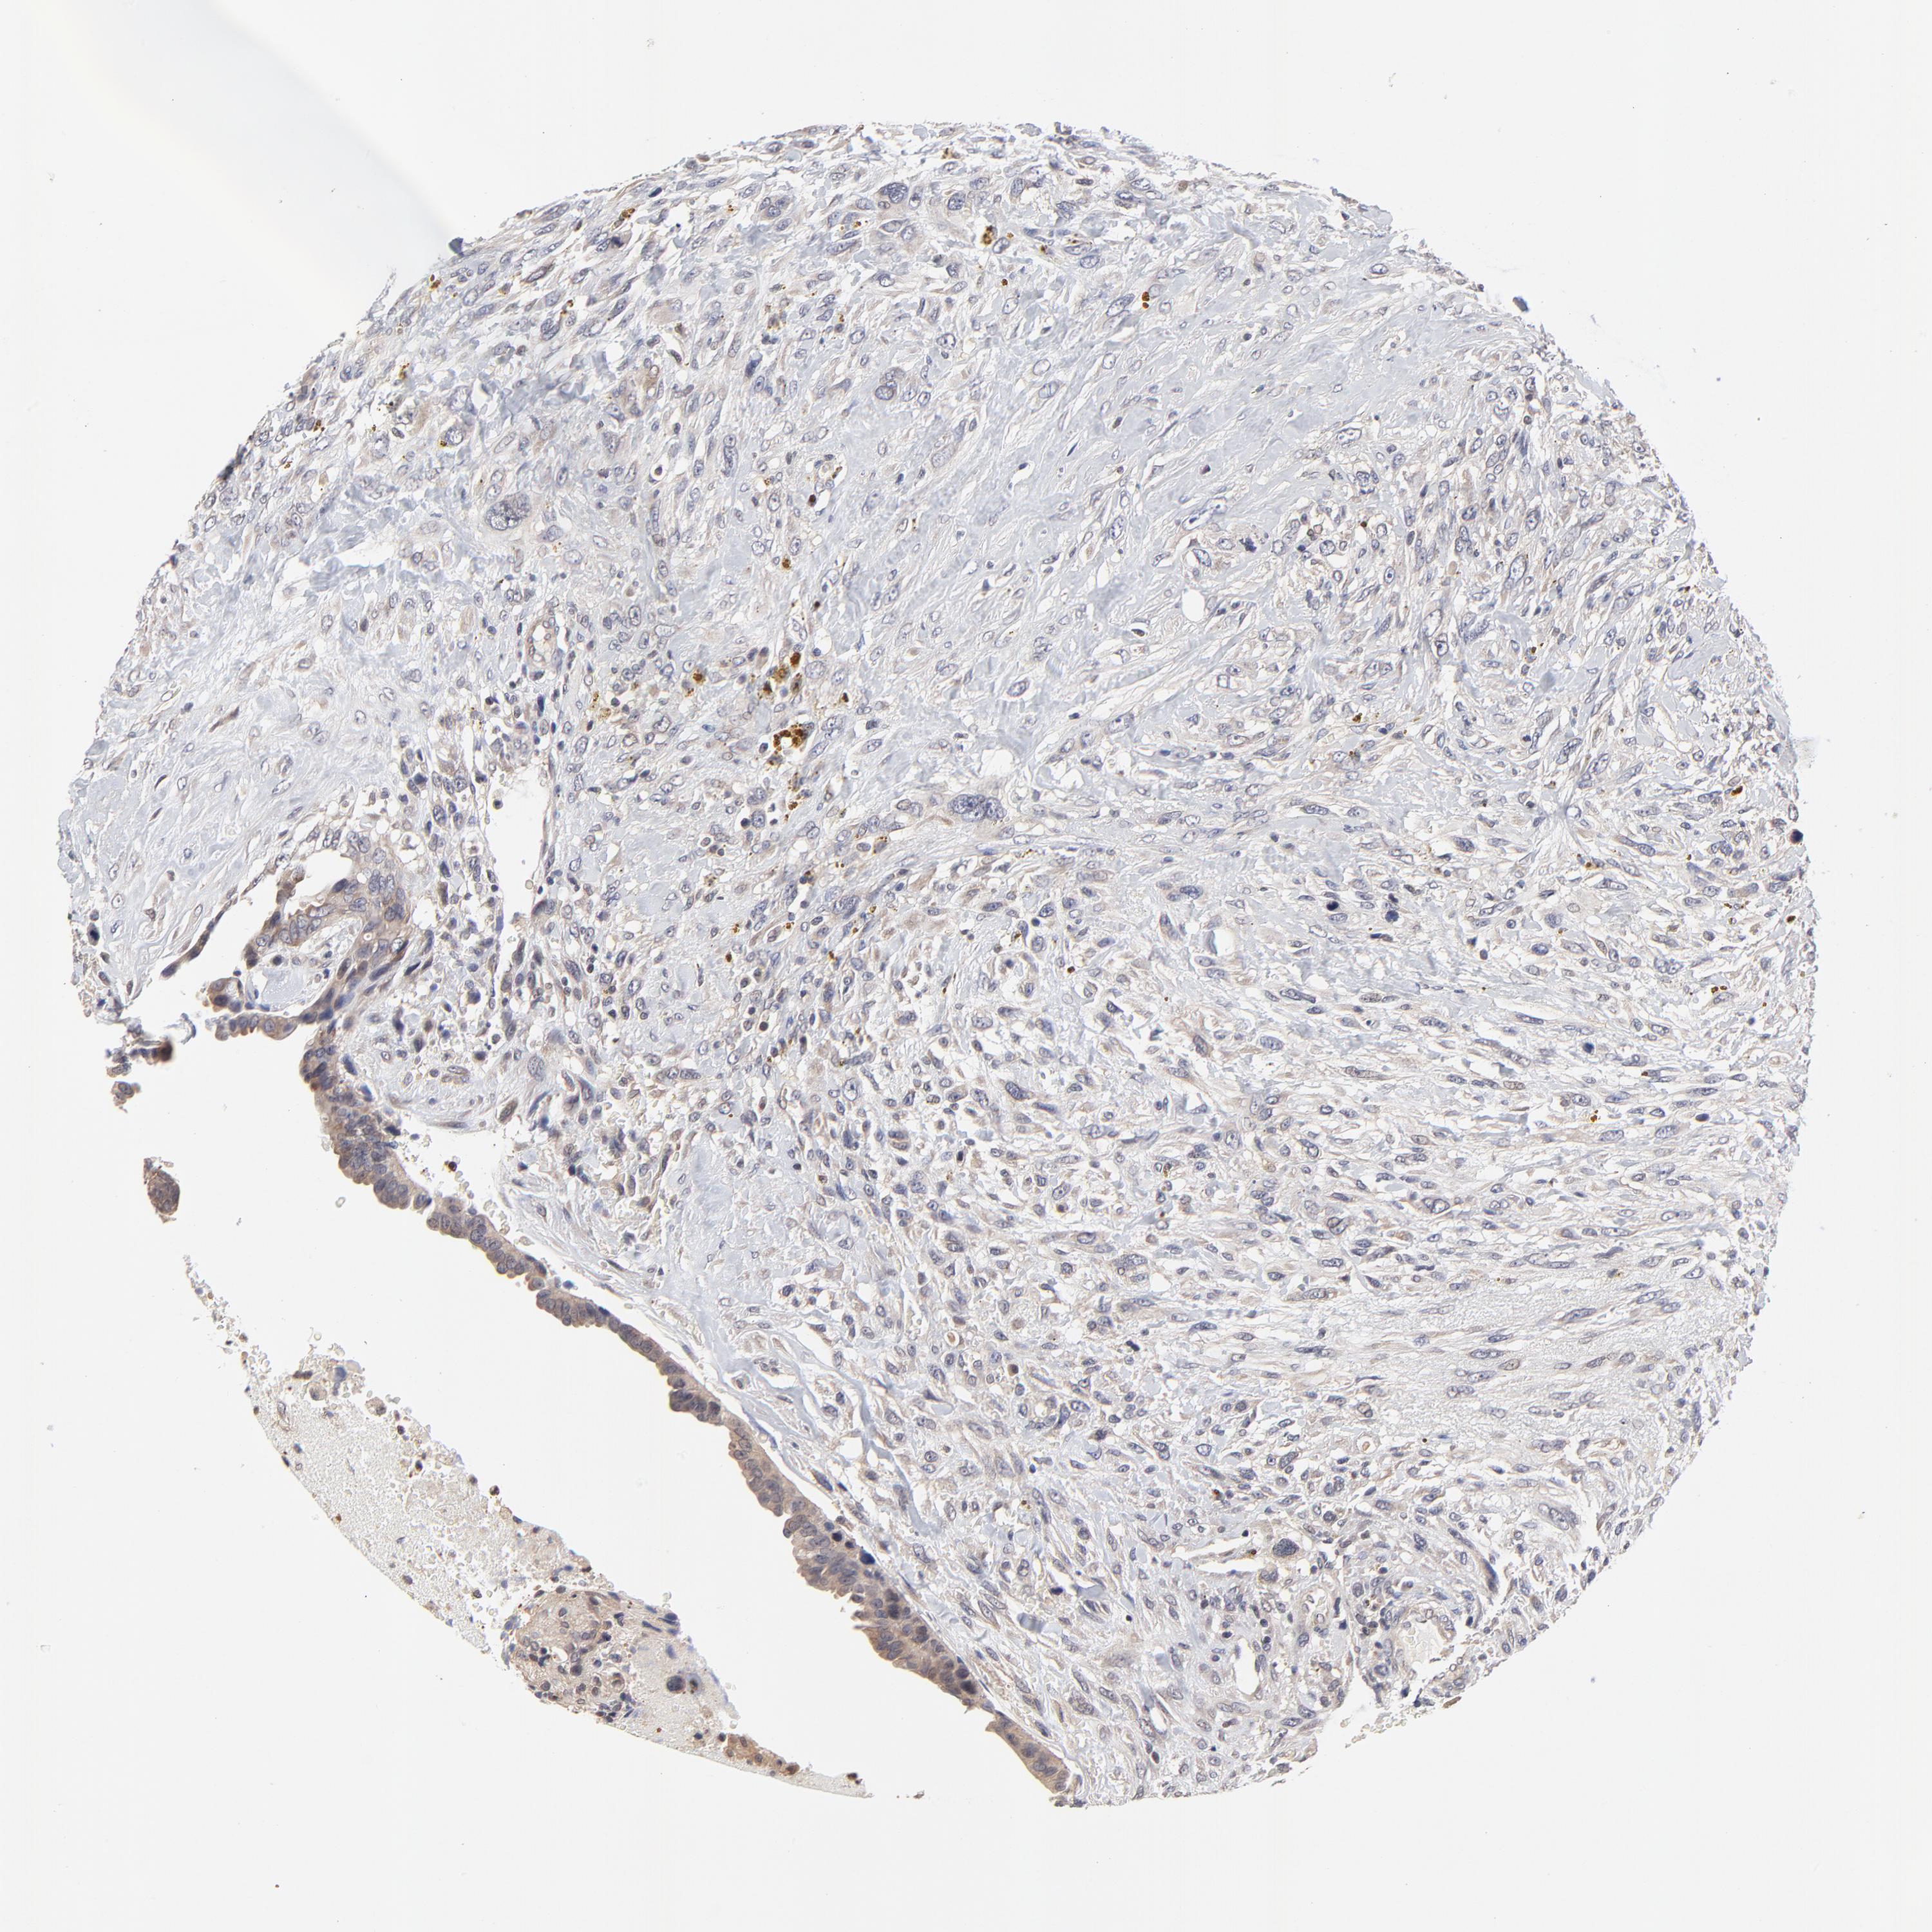

CANCER BREAST CANCER Show tissue menu

BRCA TCGA BRCA VALIDATION PROTEIN EXPRESSION